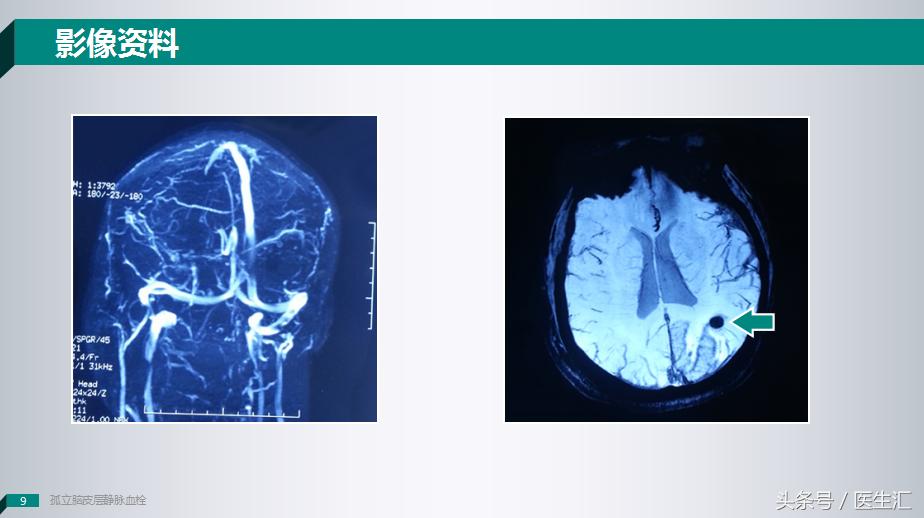

T1像上有一个长T1信号,但是这个长T1信号和T2信号和常见的脑梗死病灶并不是很相似,是沿着脑沟及脑回这样一个病变。

在弥散像上我们看到一个类圆形的小病变。

这个时候我们给患者做了一个SWI头颅磁敏感加权成像上提示这个病灶可能是一个出血的病变,但是我们给患者做MRV成像的时候却发现也没有什么问题。

因为这个患者贴近皮层,所以我们就给患者做了一个DSA的检查,我们可以看到这个患者患侧的大脑上静脉是有的,但是枕叶静脉是明显缺失的。

所以说这个时候我们应该可以确诊了,这个病人是一个少见的:皮层静脉血栓。